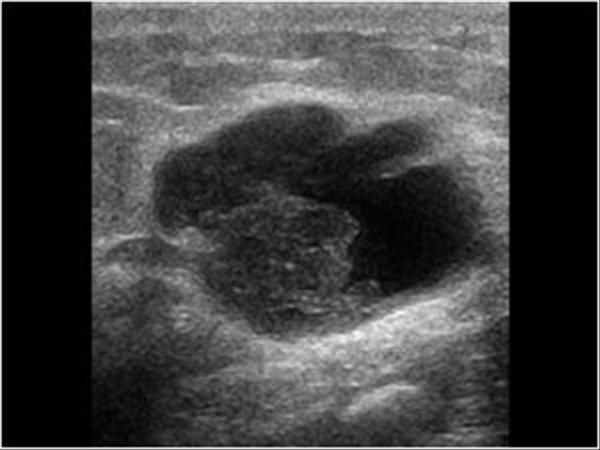

Ung thư vú

Ung thư vú - Ảnh 2

» Thông tin: Nữ giới – 82 tuổi.

» Lâm sàng: Khối tuyến vú.